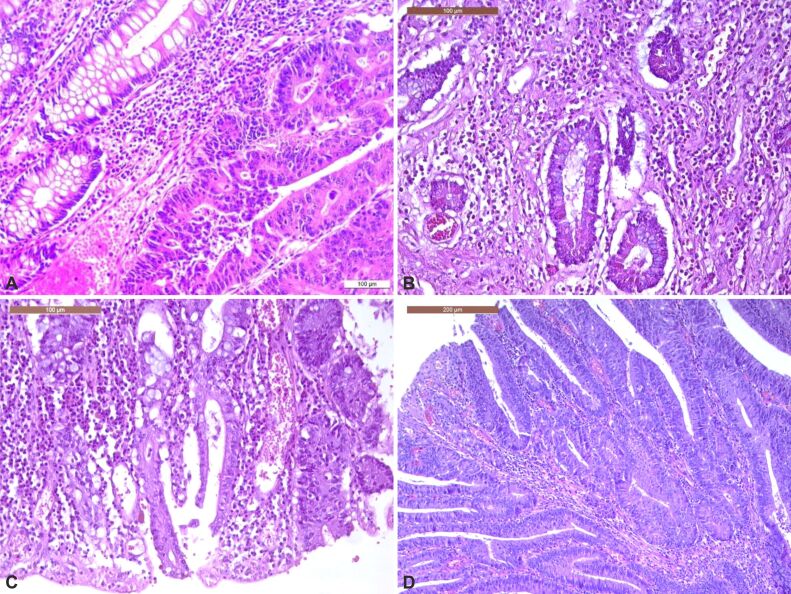

Abstract Image